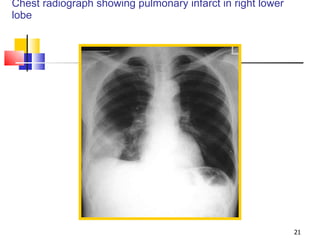

Chest radiograph showing pulmonary infarct in right lower lobe

Chest radiograph showingpulmonary infarct in right lower lobe

• #22 Figure 21-5. Chest radiograph showing pulmonary infarct in the right lower lobe. This patient had low-grade fever, hemoptysis, and pleuritic chest pain. The ventilation-perfusion scan was read as high probability for pulmonary embolism. A pleural-based density in the lower lobe with the convexity directed toward the hilum signifies pulmonary infarction. This sign is also known as ?Hampton’s hump.”